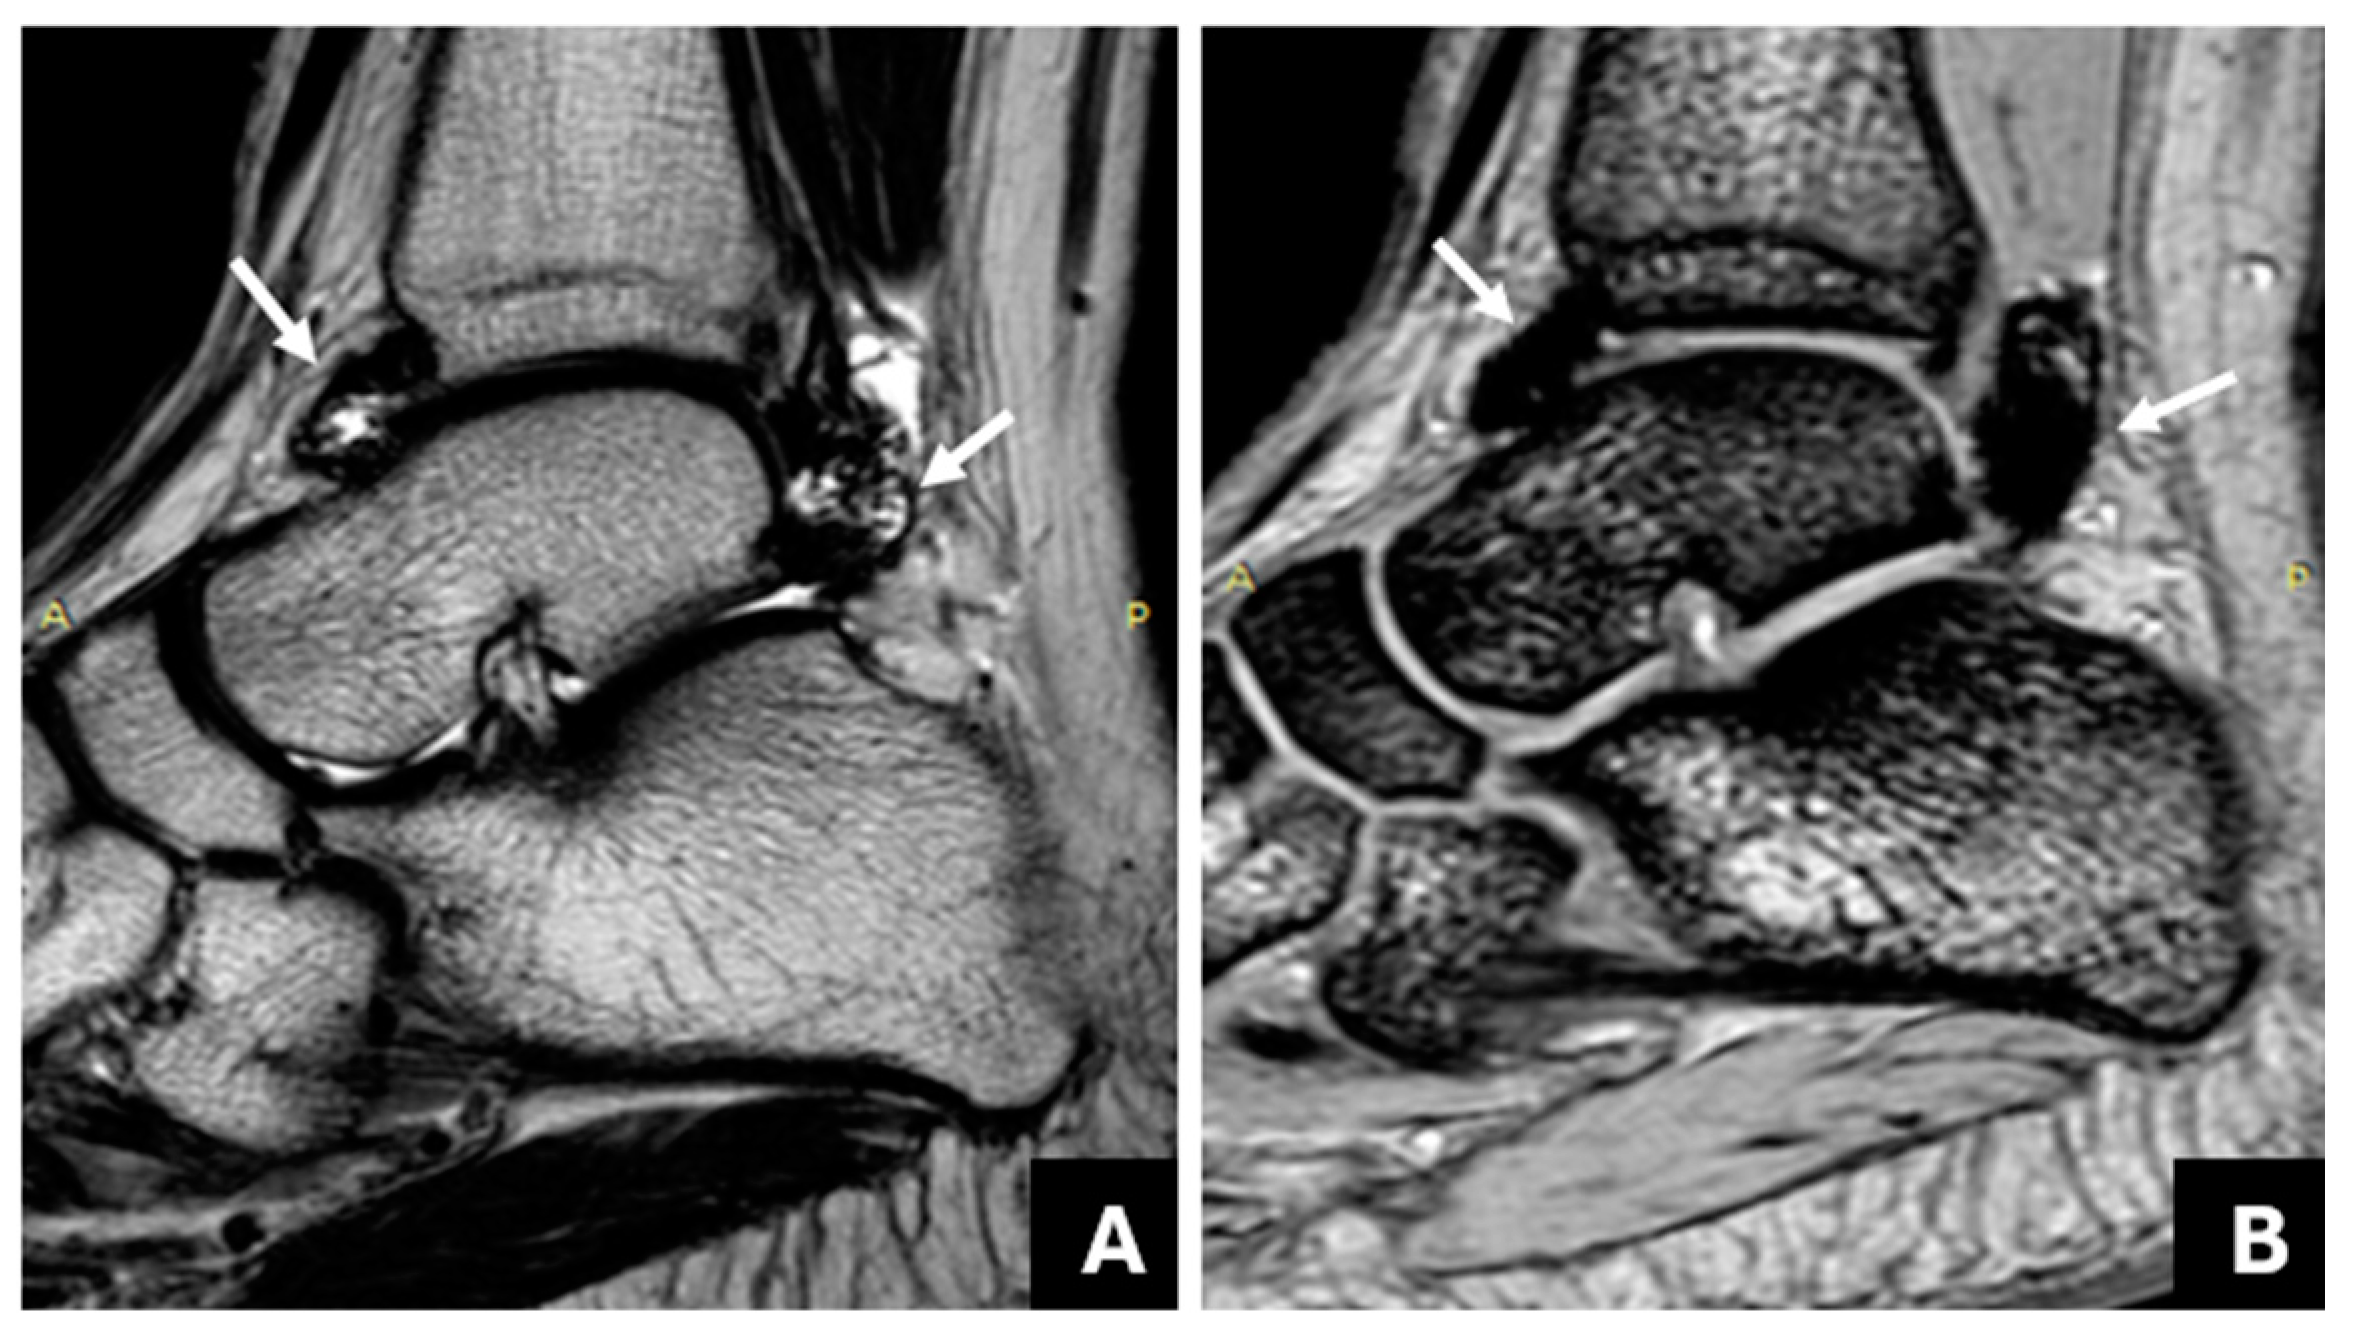

3.2. The Association of Joint Hemosiderin Deposition with Synovial Thickening, Effusion, and Osteochondral Changes (OCC)

3.3. Association of Joint Hemosiderin Deposition with the Number and Chronicity of Joint Bleeds and Clinical Score